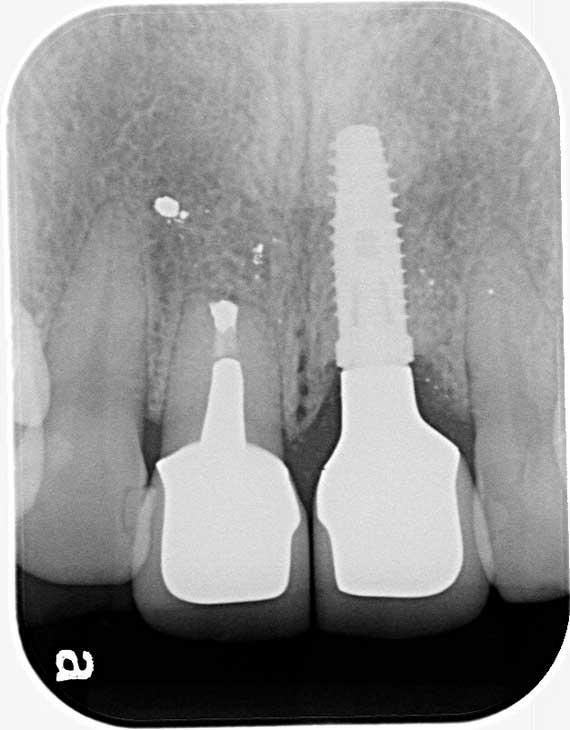

少し歯周病が進んでいたため、衛生士による歯周治療を進めながら、かみ合わせもチェック。その後、左前歯にインプラントを1本埋入し、右側とあわせて2本の前歯について、審美性の高いかぶせ物であるオールセラミッククラウンで補綴治療を行いました。

他院で抜歯した左前歯の骨の状態が良くなかったため、まず骨造成を行い、その後インプラントを1本植立しました。インプラント植立した左前歯と一緒に右前歯にもかぶせ物治療を施し、3~4か月仮歯を装着して頂きながら、2本のバランスや対合する歯とのかみ合わせ、また色や形の調整を丁寧に行いました。